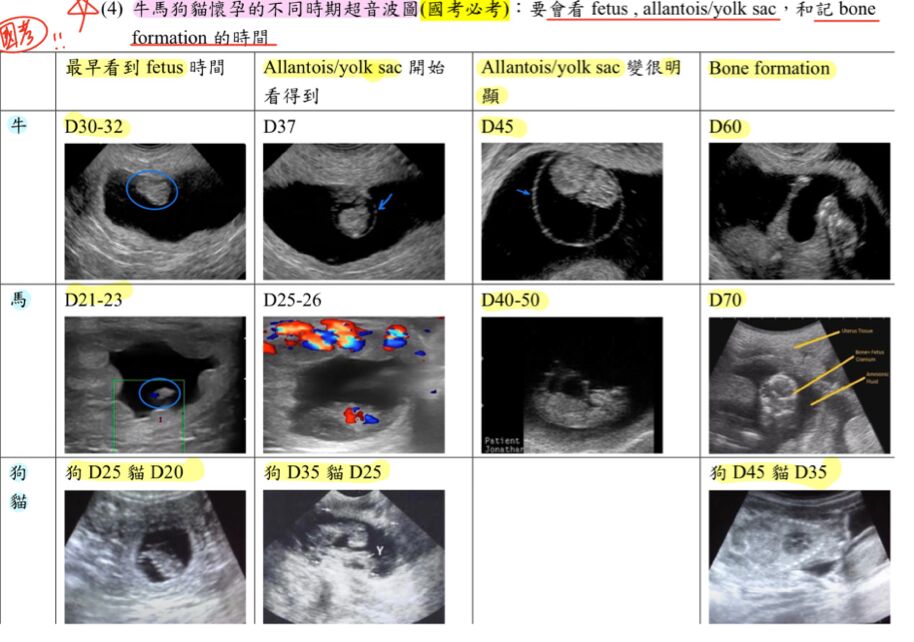

72.牧場牛隻配種後 60 天進行超音波妊娠檢查,於配種後未見發情,其子宮超音波影像如下圖,何者為該牛隻最可能之診斷?

這張圖片應該是45天的模樣

60 天時應該要有Bone formation了